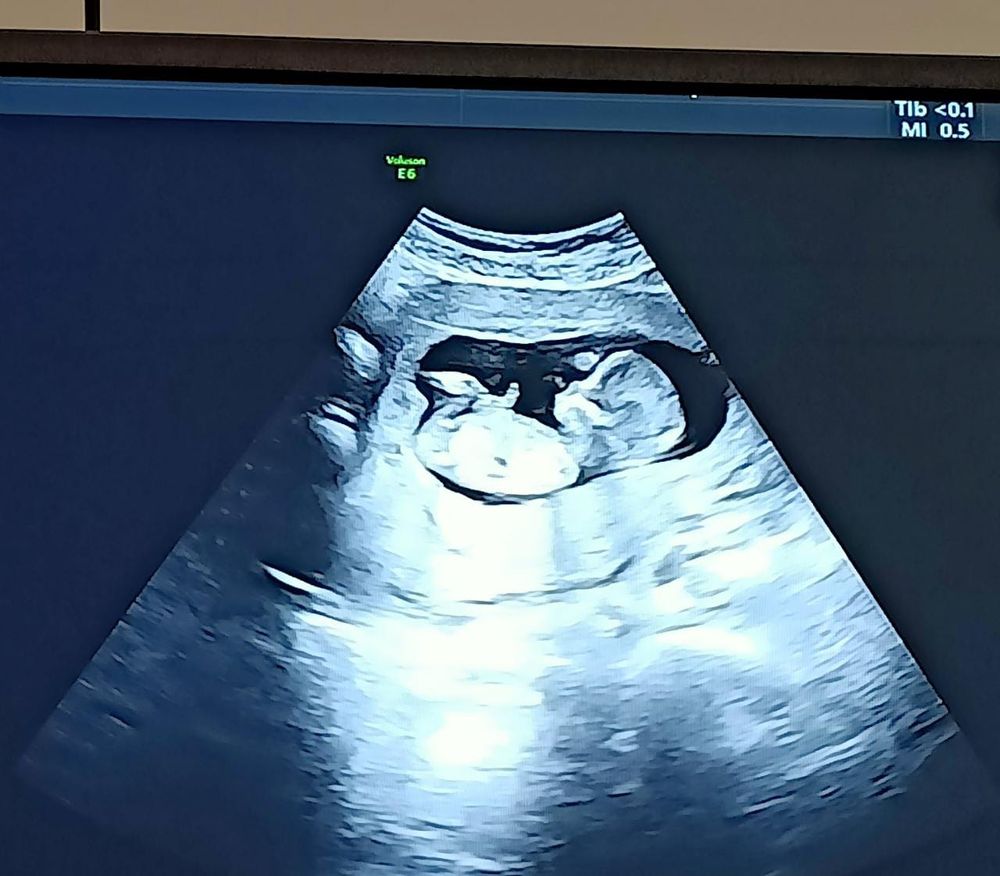

Первый скриниг ✅

Ну что ж, вот такие мы уже большие, по УЗИ всё хорошо сказали, 66мм аж 😃 кровь только в четверг результаты будут 😏 с ума сойду пока дождусь.

Ксения , вот только забрала результаты крови - все риски низкие, только возможна преэклампсия в третьем триместре, но с этим справлюсь ✊🏼 по узи всё хорошо! Малышок вертлявый и уже такой моооооой 💞💞💞